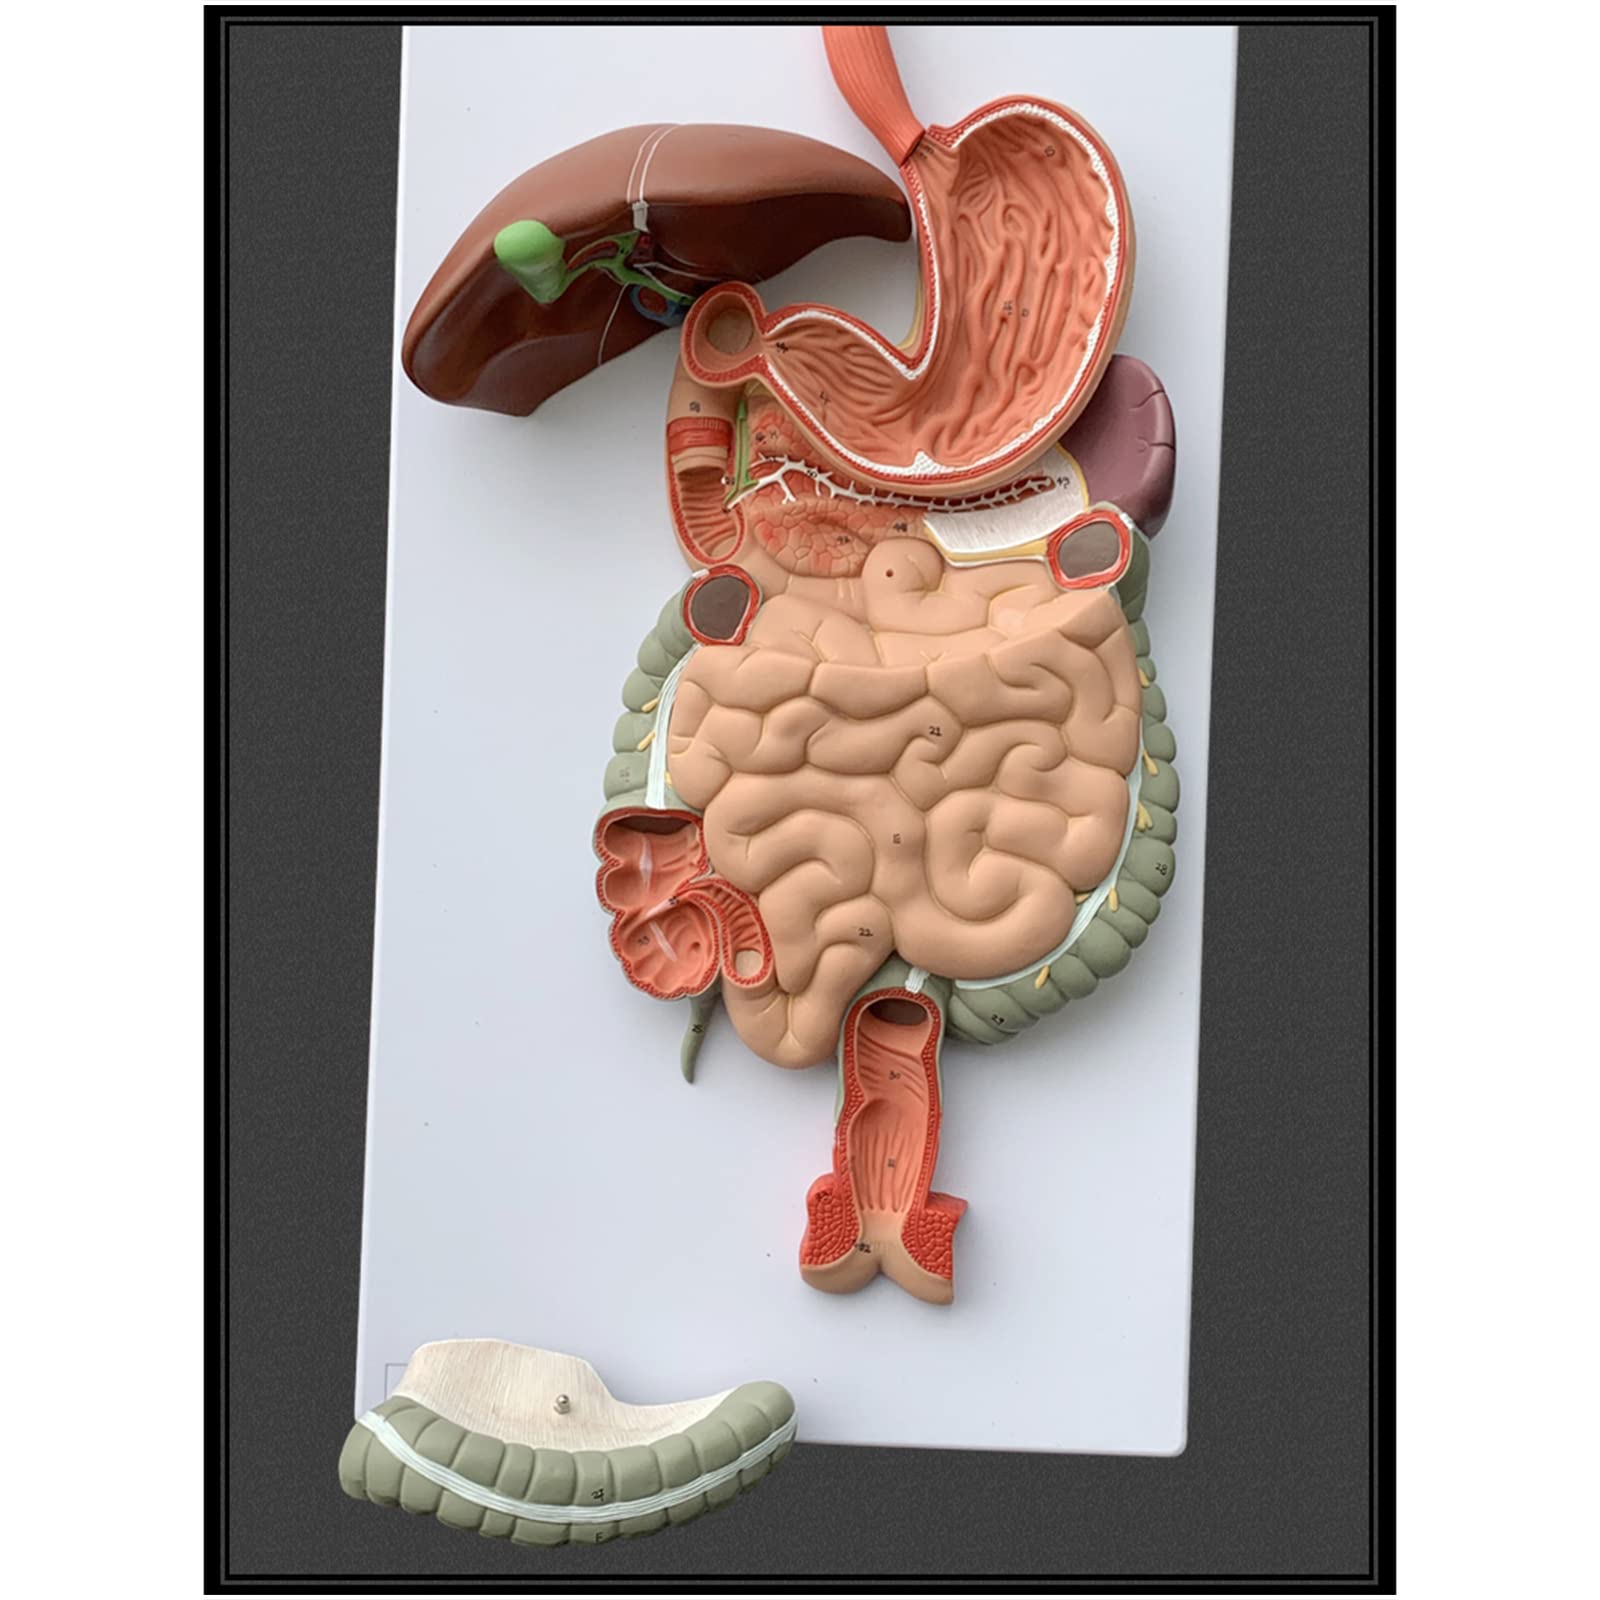

- INTERACTIVE LEARNING EXPERIENCE - Disassemble and explore the digestive system like never before!

The Human Digestive System Model is a life-size, three-dimensional representation of the human digestive tract, designed for educational purposes. It features disassemblable parts for interactive learning and is made from durable, anti-corrosive PVC material, making it an essential tool for anatomy students, educators, and healthcare professionals.